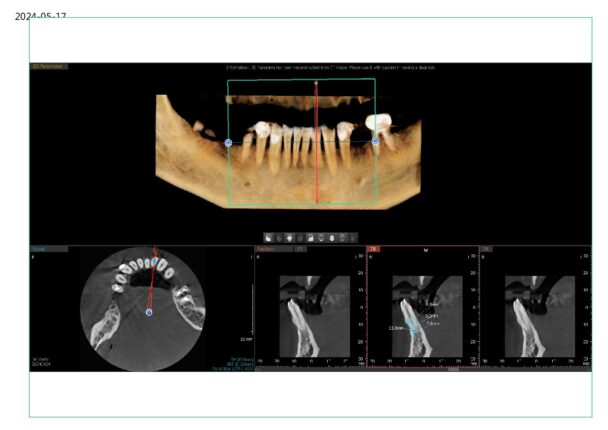

What would you do here for possible implant in 21 location? Space is limited ~6mm. My PA measures 6.5 between roots and 5.7 between crowns. I was able to get a 6mm caliper between the contacts.

1) Enamelplasty

2) Ortho to open space

3) 3.2mm diameter implant

I would do enamelplasty and a narrow implant. Ortho treatment for these cases can be more ideal, but in some cases can tip the roots in a way that may be more restrictive